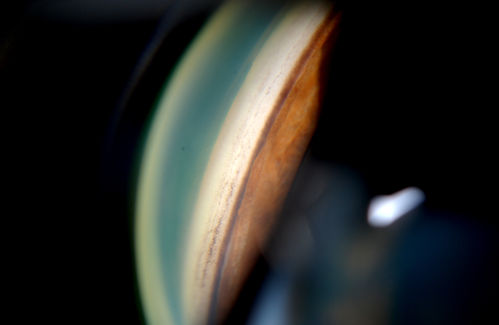

Gonioscopy; Scattered Peripheral Anterior Synechiae

Patient comes in for evaluation for glaucoma. Patient also has a history of Uveitis. Last flare up was back in 1990. Patient's VA was 20/30, Right eye and 20/40-1, Left eye. Slit Lamp Gonioscopy reveals iris bow with scattered PAS around the angles of the anterior chamber. You can also see pigmentation in the trabecular meshwork. Patient will follow up in 3-months.